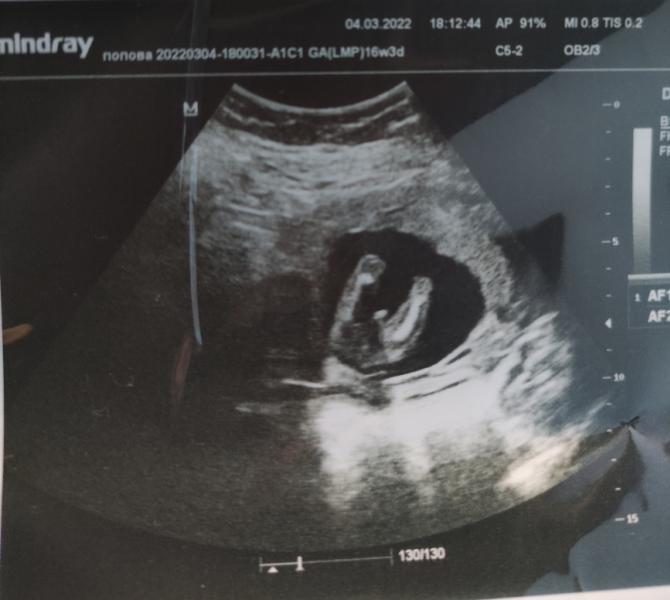

У нас будет мальчишка 🥰😊

Ну она смотрела со всех ракурсов, как можно было...девочку искала))) но не нашла